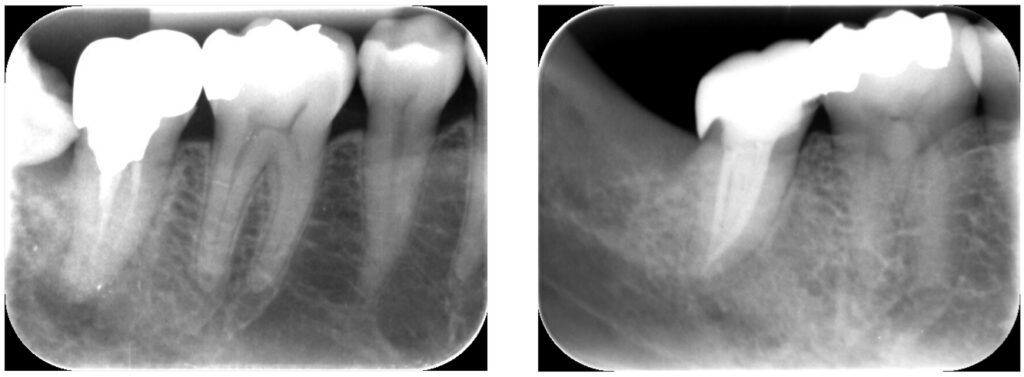

症例32:根尖性歯周炎

何もしてなくても痛い、噛んだら痛い

50代男性、他院で治療途中の歯を精密根管治療させていただきました。

3回(術後1年)

根尖部の炎症の改善、再感染の防止を行いました。